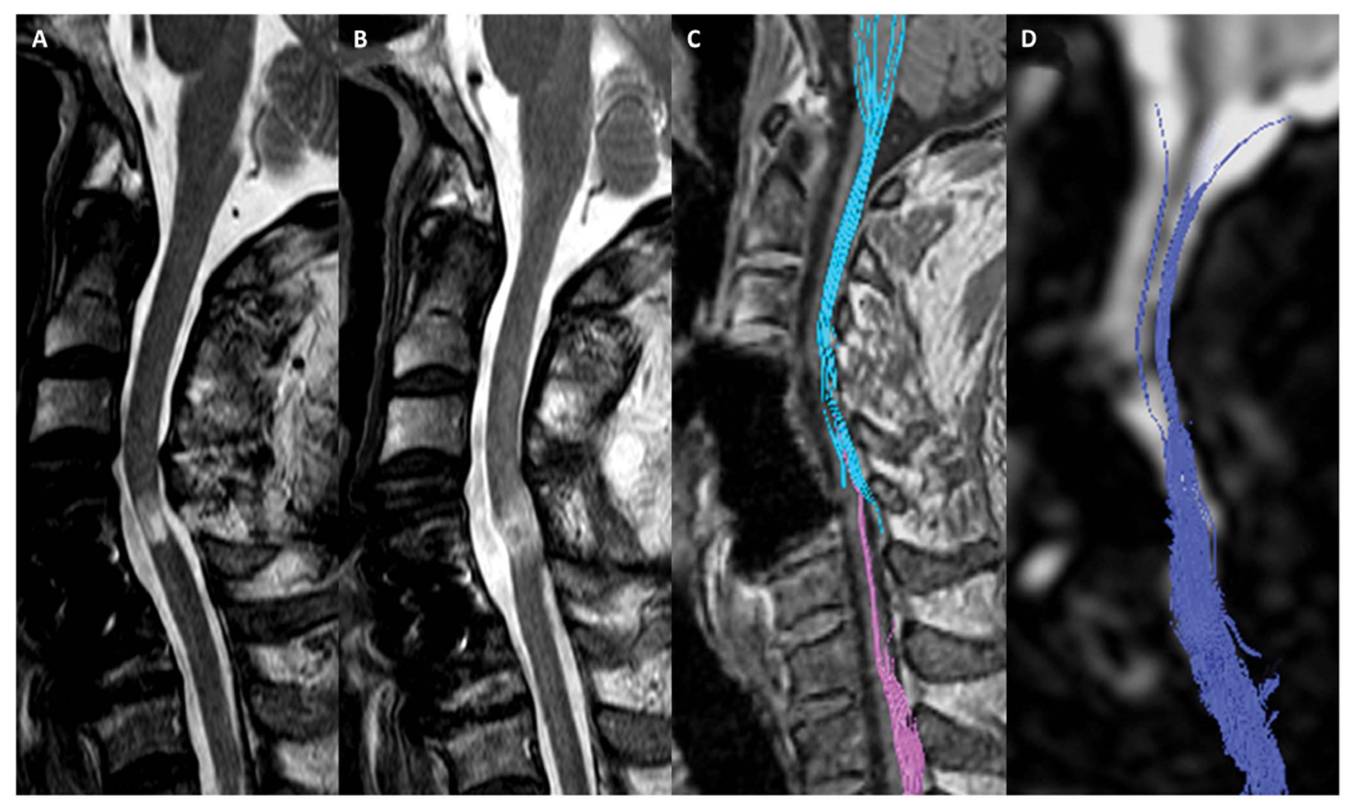

이어 “그러나 줄기세포치료제를 단회 투여했음에도 불구하고 호전된 환자의 척수 MRI 및 DTI 검사 결과 척수손상 부위에서 줄기세포치료 전에는 없던 섬유의 연속성(fibercontinunity)이 확인되는데 이는 줄기세포치료로 인한 신경재생 효과로 판단할 수 있다"고 말했다.

[환자의 DTI검사결과다. 줄기세포치료제 투여하기 전(A와C)에 비해 투여 후 6개월이경과한 후(B와 D)에는 끊어진 척수신경이 재생되었음을 확인할수 있다